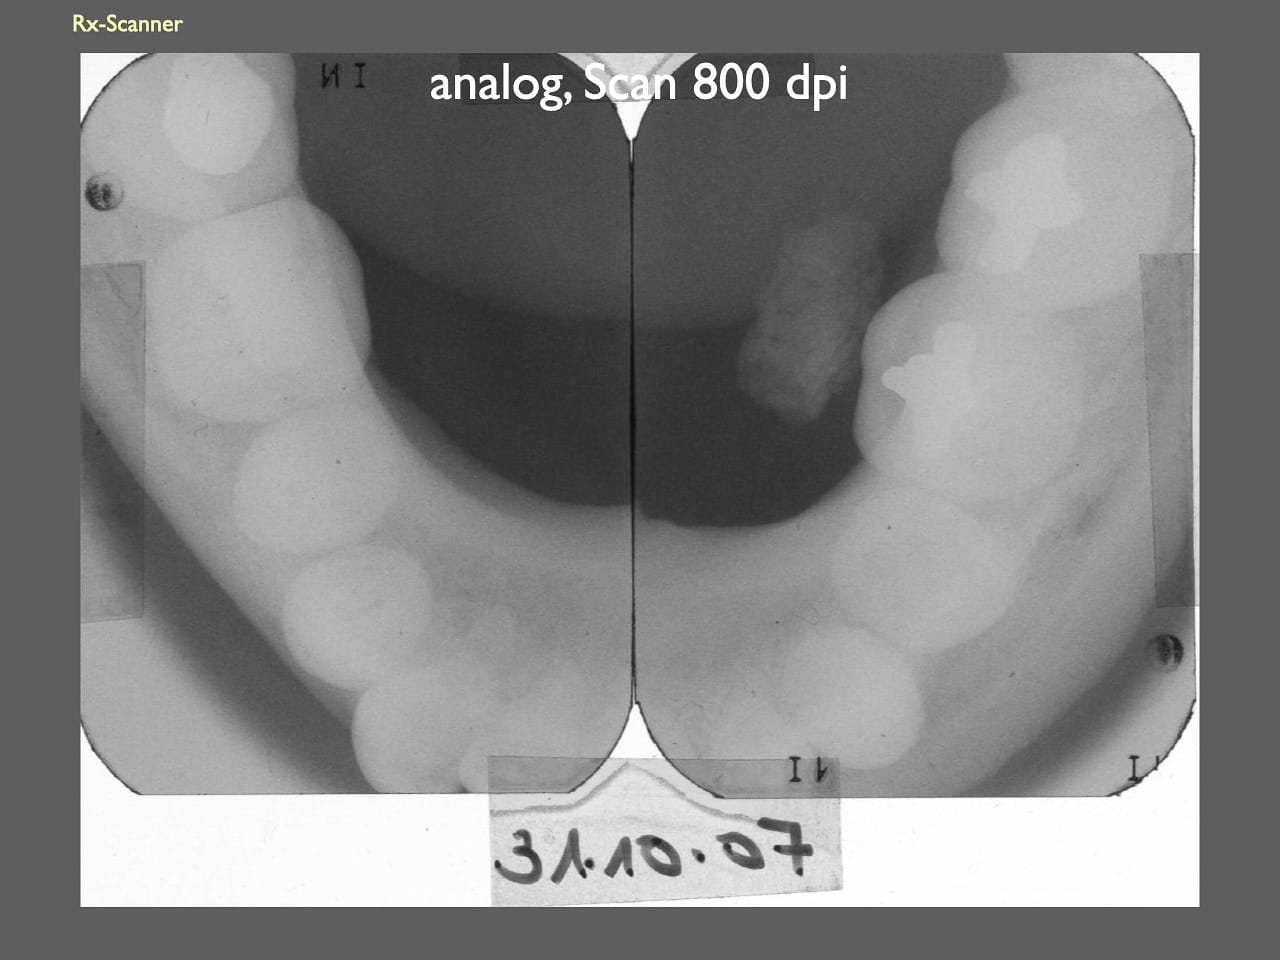

dental Scannen in der Zahnarztpraxis. Study Club vom 28.2.2010. Von peter portmann, Veröffentlicht am 28. Feb. 2010 — 3 min Lesezeit dokumentationfoto Auf dieser Seite Zahnarztpraxis-Trilogie zu Fotografie und Dokumentation Portrait Fotografie Scannen Scannen